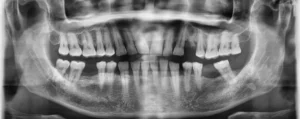

Radiografía panorámica dental: el primer paso antes de tu ortodoncia

Por Alfonso Gálvez Vargas

Iniciar un tratamiento de ortodoncia, especialmente uno tan avanzado como la ortodoncia invisible, implica mucho más que solo colocar alineadores.  Uno de los pasos fundamentales, y que marca la diferencia…

radiografía panorámica dental